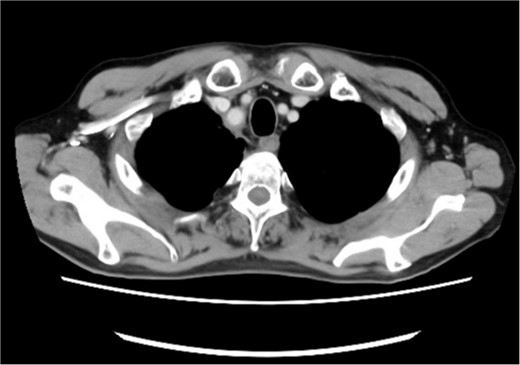

A 72-year-old man diagnosed with NSCLC was referred for possible surgical treatment of a solitary nodule detected in the mesorectum. His medical history included hypertension and endoscopic resection of colonic polyps, with no prior thromboembolism. He had received combined medical treatment for NSCLC (cT4N0M0, stage IIIA) (Fig. 1), including four courses of cisplatin and docetaxel chemotherapy with a 60 Gy/30 fractions radiation dose, followed by 1 year of consolidation therapy with durvalumab (640 mg/body). The patient tolerated the treatment well, achieving a complete response 13 months before presentation (Fig. 2). However, the mesorectal nodule was incidentally discovered during surveillance CT after NSCLC treatment completion. It was round, 15 mm in diameter, showed contrast enhancement, and was near the mesorectal vessels (Fig. 3a and b). An FDG PET/CT scan revealed a solitary mesorectal nodule with an SUVmax of 10.3 (Fig. 4). Consequently, the radiologist suggested differential diagnoses of malignant lymphoma and metastatic lymph nodes from the urinary or lower gastrointestinal tract, as NSCLC typically does not metastasize to mesorectal lymph nodes. No other abnormal FDG uptake was observed. Laboratory tests showed normal levels for tumor markers, including carcinoembryonic antigen, sialyl Lewis X (SLX), squamous cell carcinoma antigen, neuron-specific enolase, cytokeratin fragment (CYFRA), progastrin-releasing peptide, and blood coagulability was within the normal range. Total colonoscopy revealed no neoplastic lesions, and urinary cytology showed nonmalignant urothelial cells. Noninvasive diagnostic approaches, including endoscopic or CT-guided biopsy, were extensively discussed but deemed difficult because of anatomical restrictions, risk of dissemination, and procedure-related complications (such as bleeding or perforation). Because of the potential malignancy and need for en-bloc resection, we opted for surgical resection using a standardized laparoscopically assisted mesorectal excision technique. During rectal dissection, the nodule was not visible through the posterior and lateral sides because it was completely embedded in the mesorectum. Therefore, a Pfannenstiel incision was made in the lower abdomen to exteriorize the rectum after the division of the proximal colon. The nodule was confirmed by direct palpation, marked with a stitch, and subsequently removed after intracorporeal transection of the distal rectum. We inspected the resected specimen and confirmed that the nodule was incorporated (Fig. 5a and b). A colorectal anastomosis was then performed using a double-stapling technique with a circular stapler. The postoperative course was uneventful, except for a slight elevation of the d-dimer level (up to 3.26 μg/ml) on postoperative Day 7, which normalized spontaneously without intensive anticoagulation therapy. The patient was discharged on postoperative Day 10. Pathological examination revealed that the 7-mm white nodule was an intravenous organized thrombus in the mesorectum surrounded by granulation tissue, with no malignancy observed (Fig. 6a and b). Postoperatively, the patient did not require additional chemotherapy or anticoagulation therapy. During the 16-month follow-up, no radiological evidence of NSCLC recurrence and thromboembolism was detected (Fig. 7).

Preoperative pelvic computed tomography (CT) image. The circle indicates the nodule located in the mesorectum. (a) Horizontal view. (b) Sagittal view.